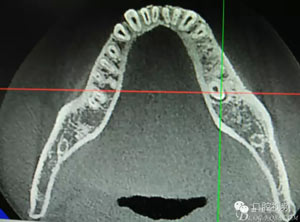

圖2.術(shù)前的CBCT,35移位至36、37之間的舌側(cè)。